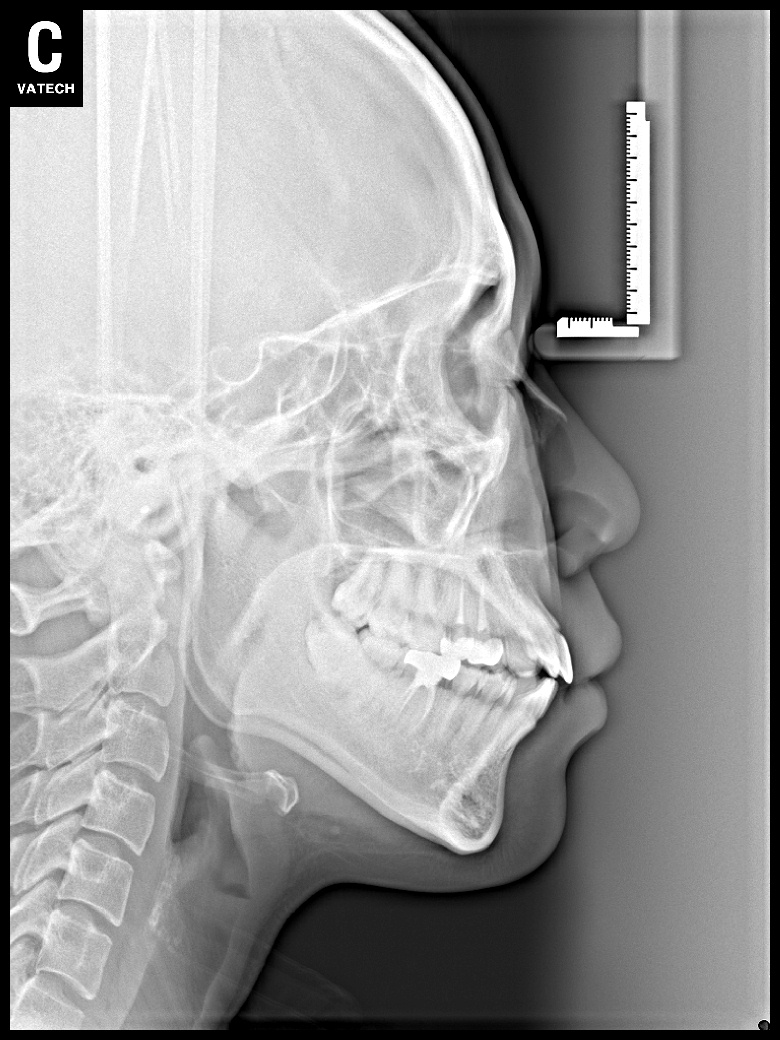

치료 후 사진입니다.